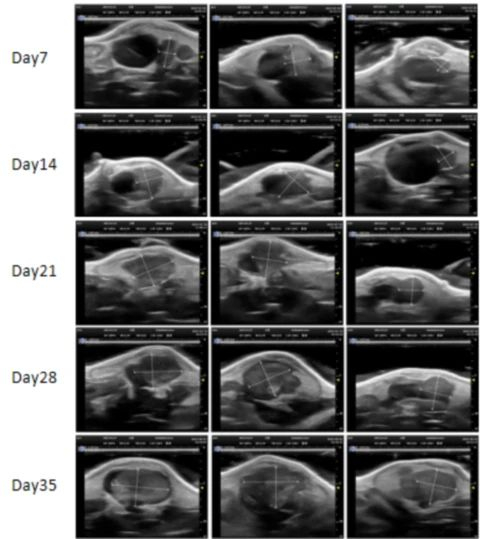

PDX Model (Growth Curve)

部分beats365PDX原位模型展示

部分beats365PDX原位模型展示